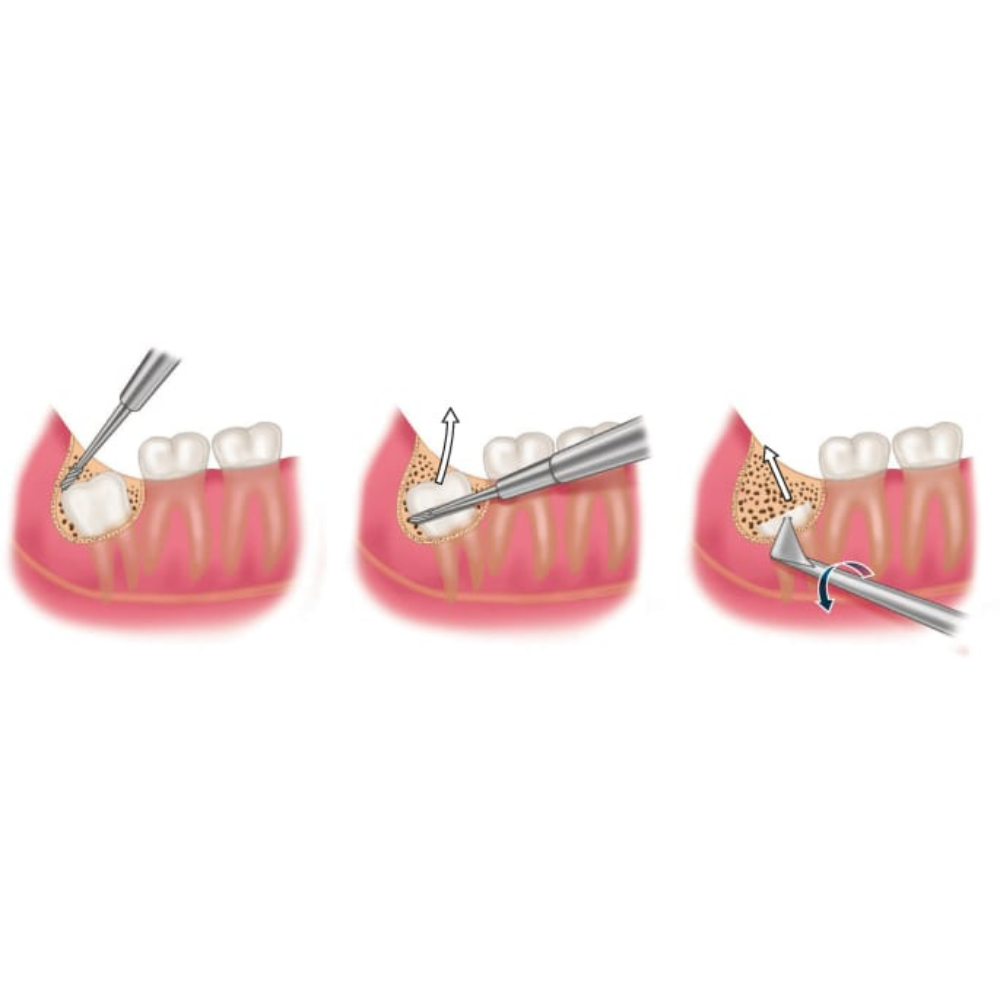

Wisdom Teeth Removal

At Kiaan Dental Lounge, wisdom tooth extractions are carried out with a strong focus on patient comfort, ensuring a well-planned, smooth, and virtually pain-free experience, along with careful post-operative guidance for quick healing and recovery.